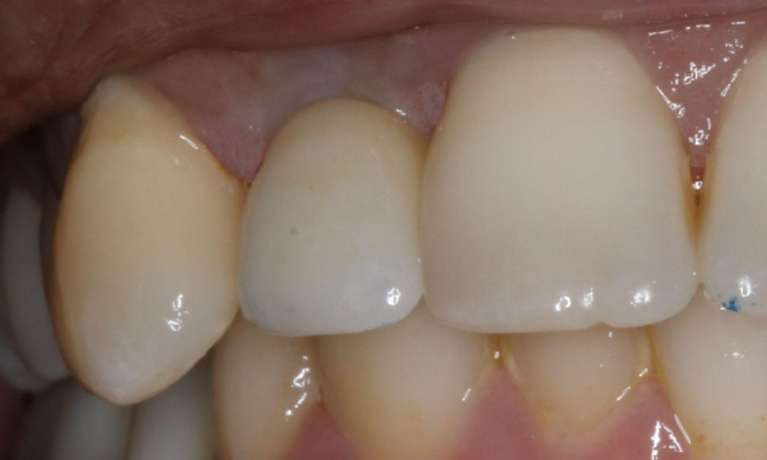

For this patient, dental implants were used to replace missing back teeth to help reestablish chewing efficiency and improve overall oral function.